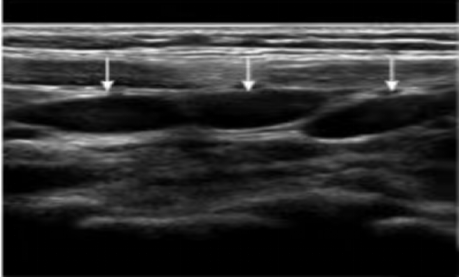

肠系膜淋巴结(箭头所指)

由此可见,超声在肠系膜淋巴结炎诊断中占有很重要的地位,它因无创伤且无辐射等优势,已成为临床不可或缺的检查手段。